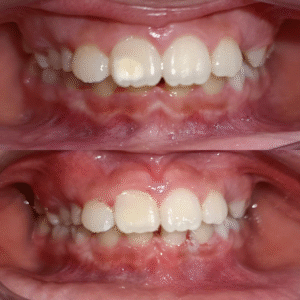

Niềng răng thẩm mỹ

- Niềng răng mắc cài

- Niềng răng với khay trong suốt

- Niềng răng cho trẻ em

- Niềng răng cho người trung niên

- Niềng răng những ca khó, phức tạp, lệch mặt, lệch hàm

Cải thiện hàm răng đều và nụ cười duyên dáng với các giải pháp niềng răng hiện đại, thẩm mỹ cao.